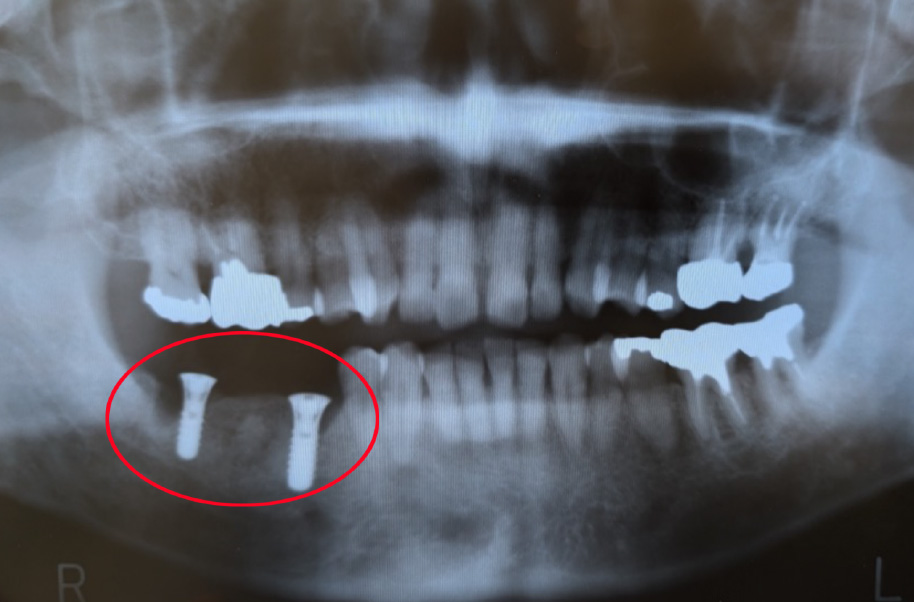

【インプラント埋入直後】

2009年10月40歳

【16年後】

2025年3月56歳

- 割れてしまった歯の代わりにインプラントを1本埋入し、しっかりと噛める状態を取り戻しました。